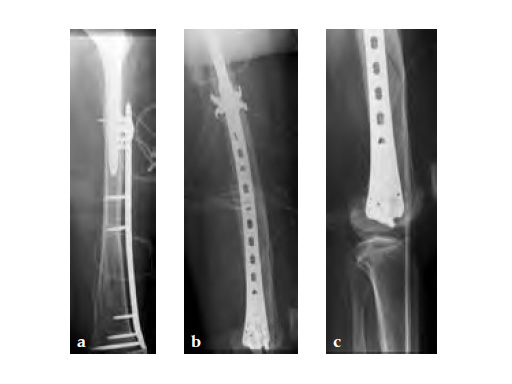

Case 2: A 76-year-old female with a Vancouver type C fracture.